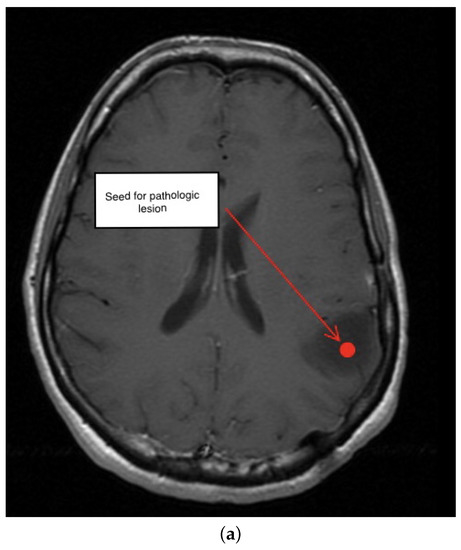

3.3. Third Scenario